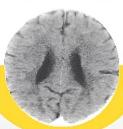

POR DENTRO DO CÉREBRO

Estas são imagens dos cérebros de duas crianças de 3 anos. O menor tamanho e os espaços escuros indicam lacunas no desenvolvimento, causadas pela negligência e pela falta de afeto

Desenvolvimento regular

Extrema negligência